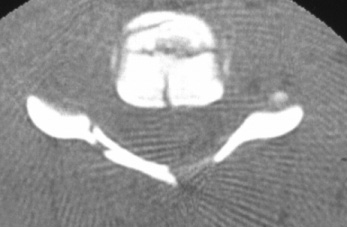

Fractura

Jefferson

Fractura Jefferson Fragmente

osoase la stanga apofizei odontoide

Fractura Jefferson Fractura spanzuratului

Aspect CT